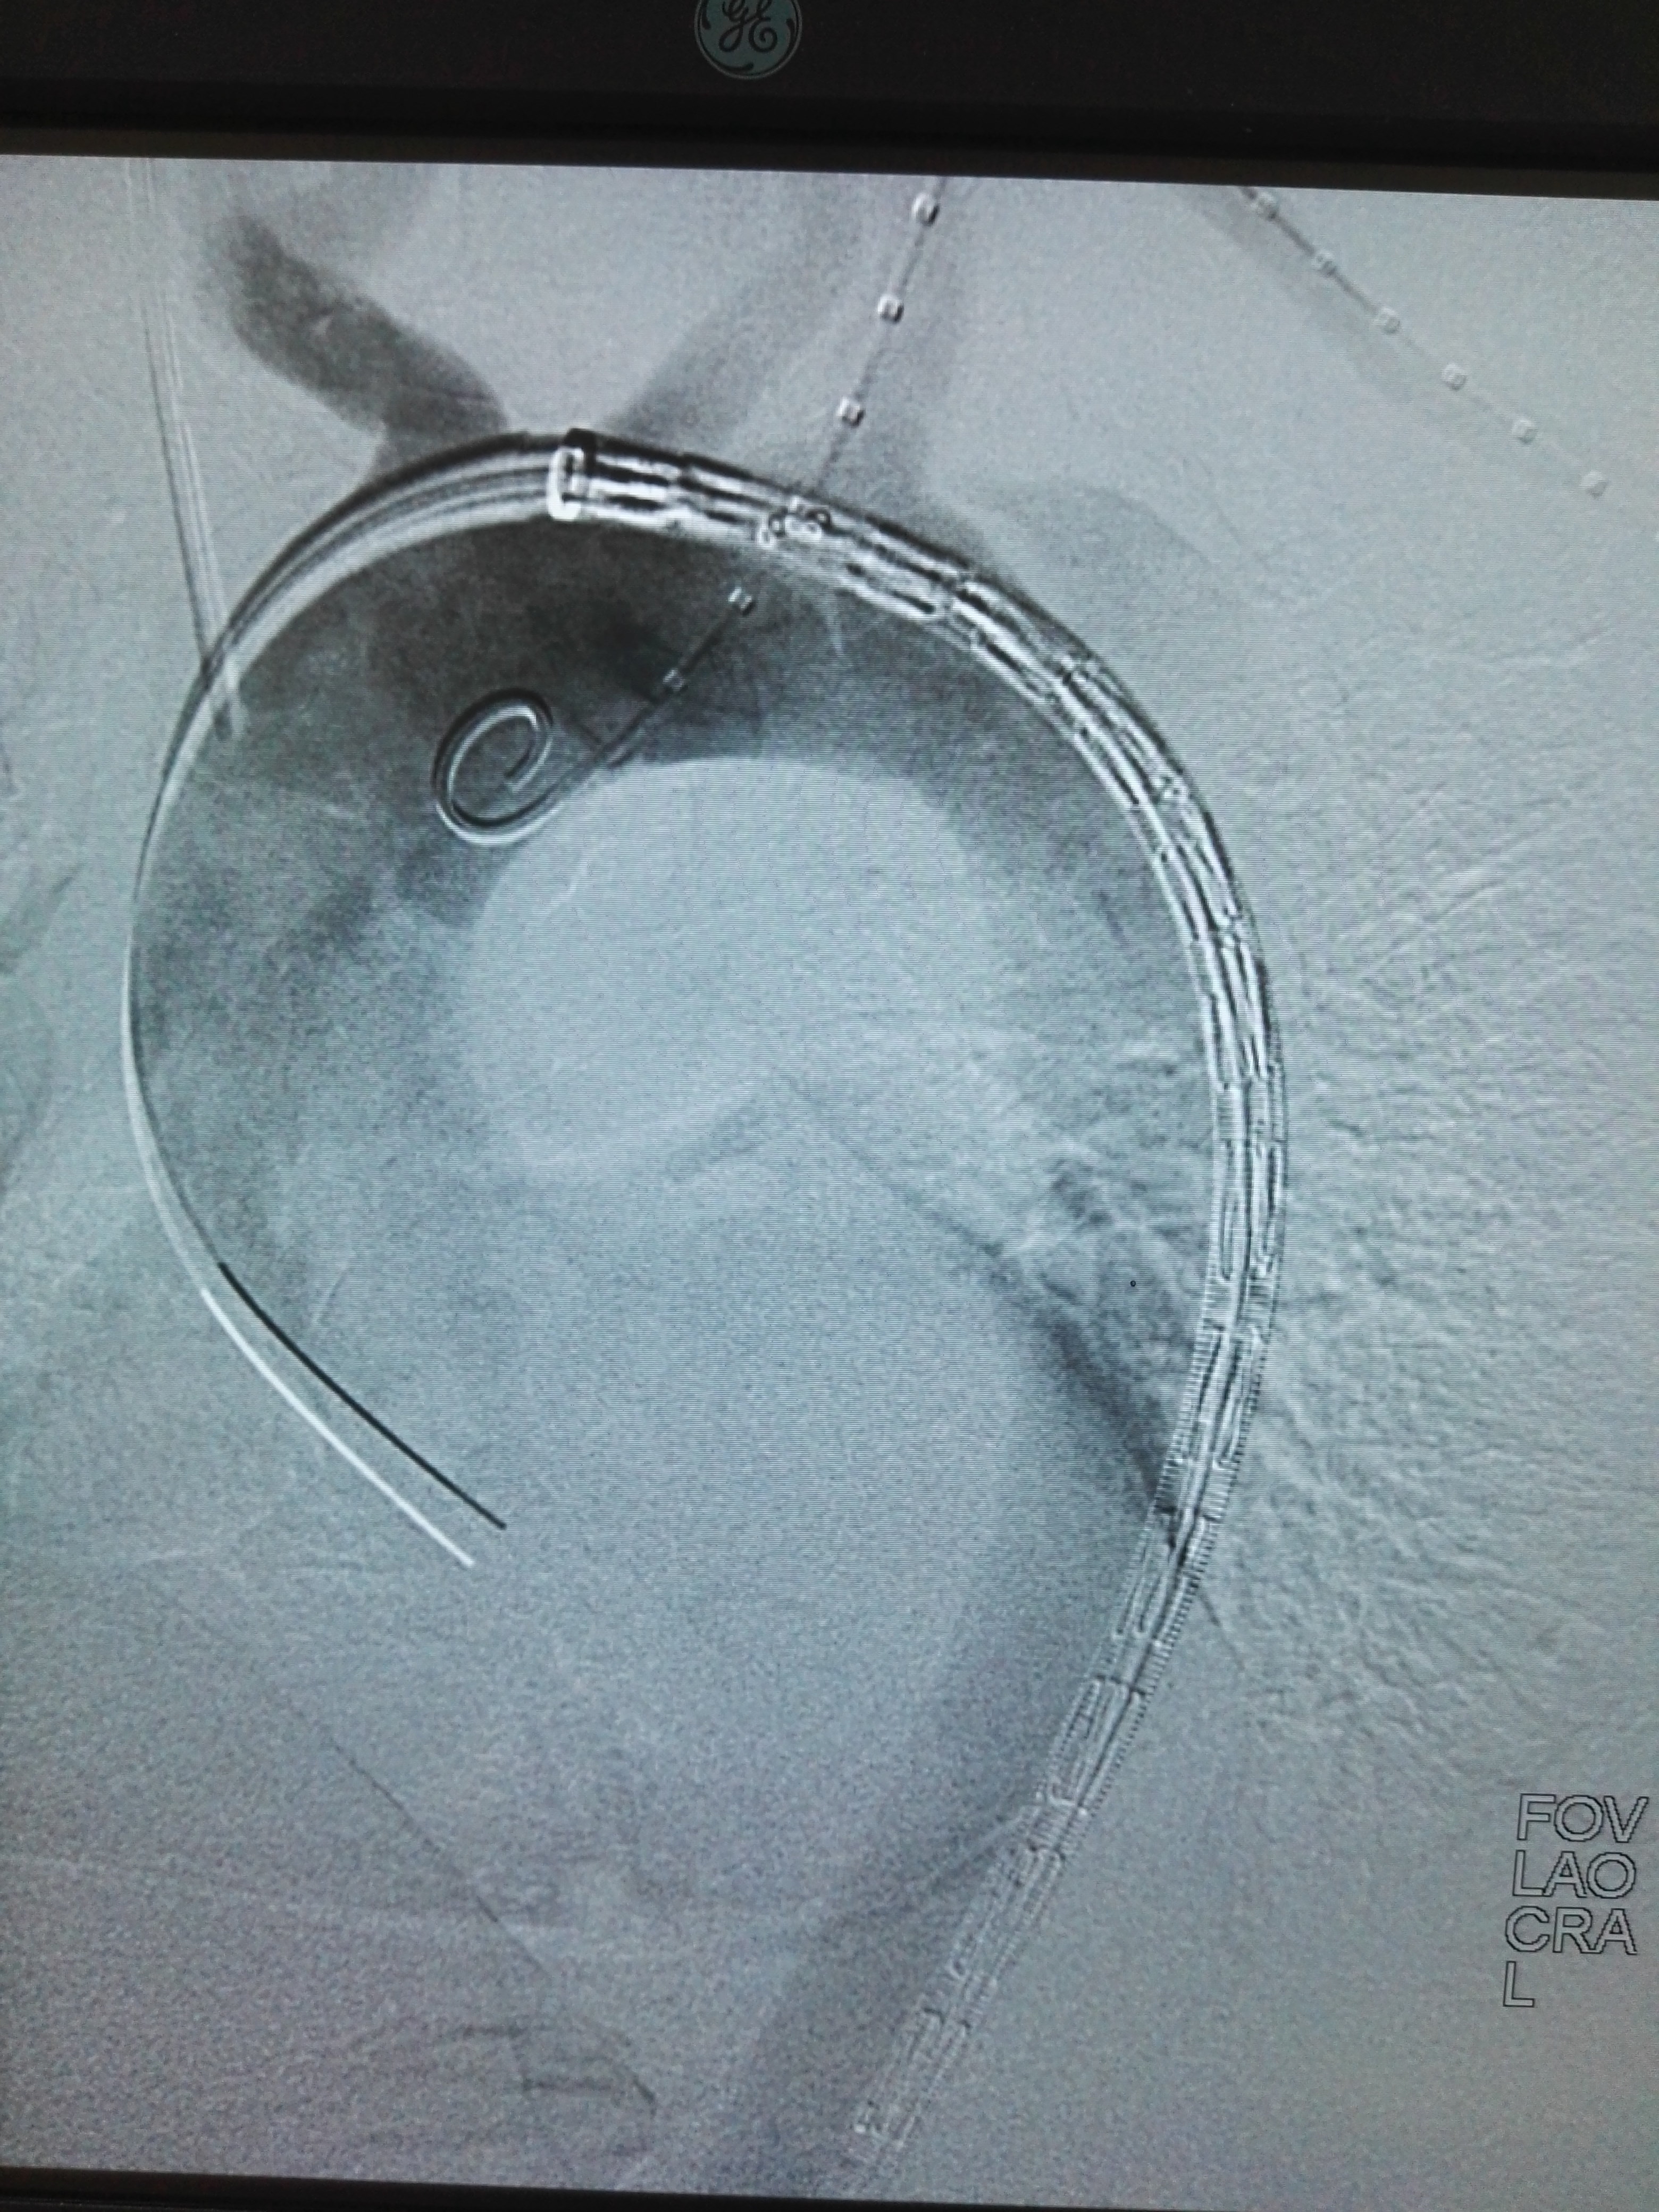

主动脉瘤和主动脉夹层

哪些是主动脉夹层动脉瘤?

主动脉夹层动脉瘤是由心脏胃壁断裂,尤其是大动脉胃壁断裂后,胃壁撕裂后血流踏入神经